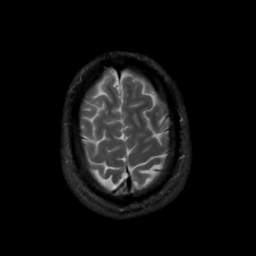

MR Study #15, June 9, 1991 -- Slice #43

[Home][Help][Clinical][Tour 1][Tour 2] Slice 43